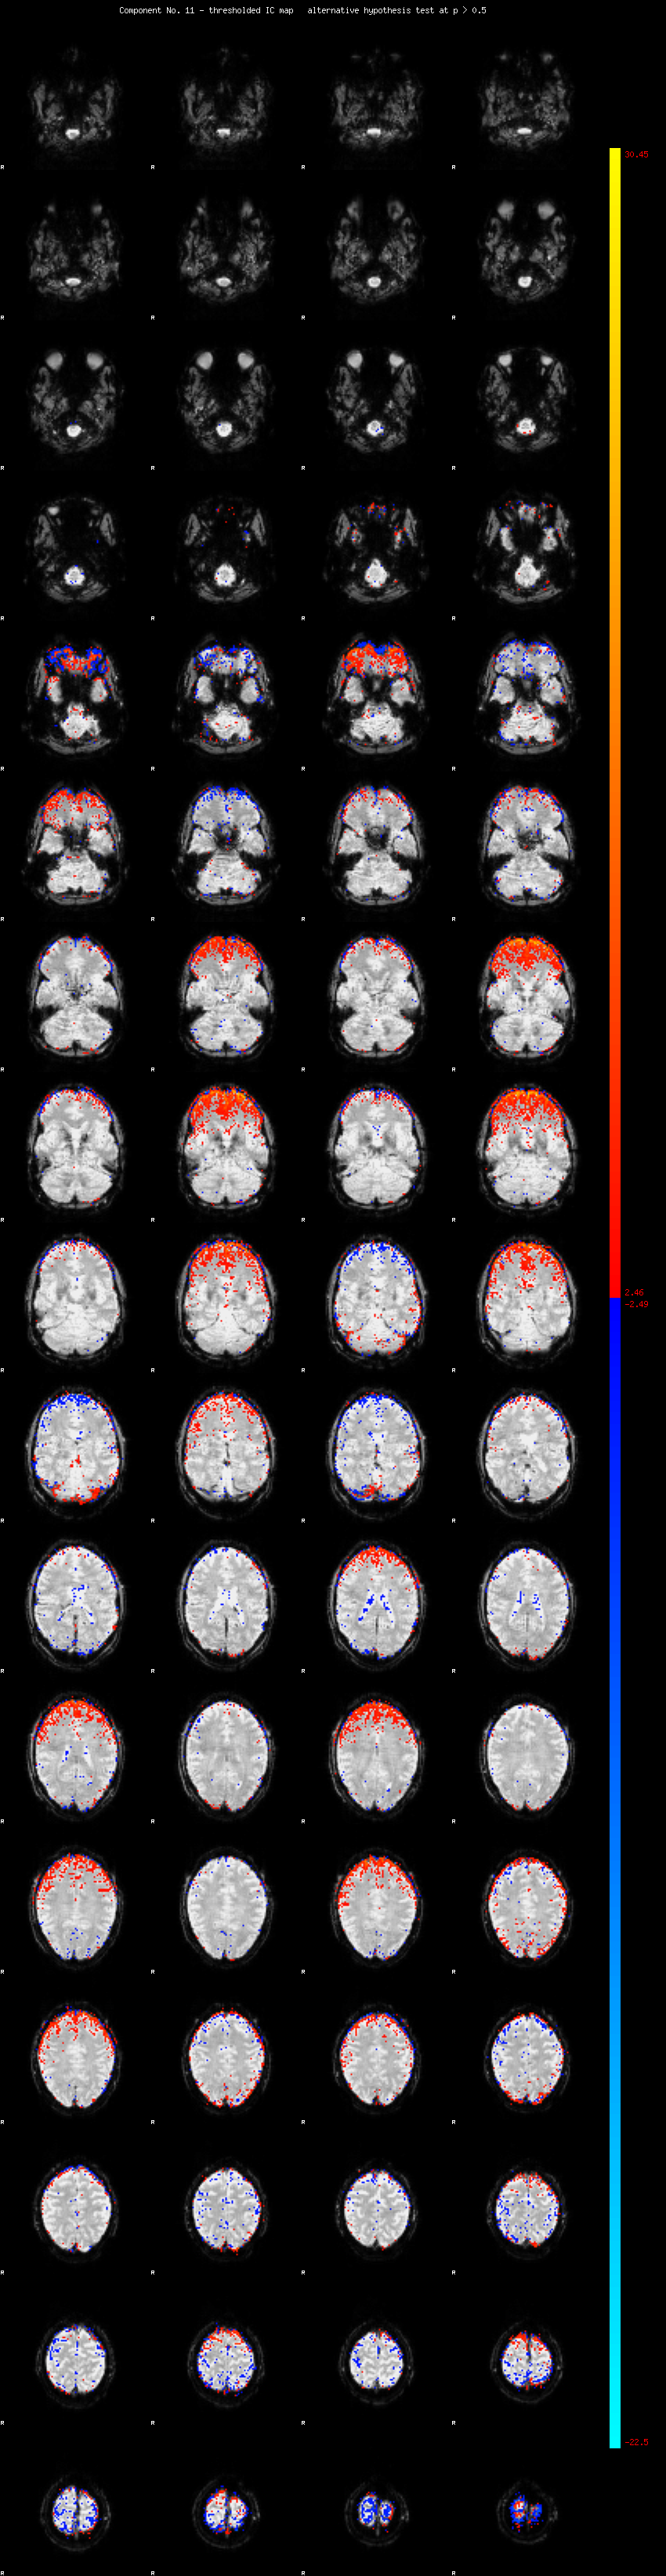

MELODIC Component 11

2.05 % of explained variance;     1.36 % of total variance